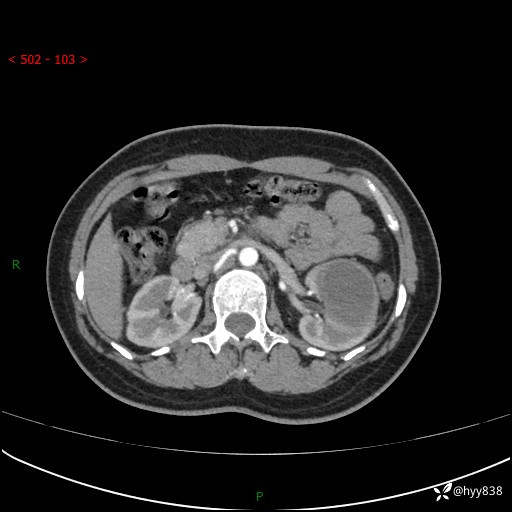

现病史:患者于1周前因左侧腰腹部间断胀痛不适,无恶心呕吐,无明显肉眼血尿,无畏寒发热,无尿频尿急,起病初,患者来我院就诊,查CT提示左肾低密度影,外周血提示:白细胞11.25*10^9/L.行抗感染治疗后未见明显好转,06-18泌尿系增强CT提示左肾类圆形低密度占位(脓肿?肿瘤?),大小:4.0*3.2cm,为求进一步治疗,门诊以“左肾占位”收住我科。 起病以来,患者精神佳,饮食、睡眠良好,大小便正常,体力体重无明显变化。

双肾CT平扫+增强